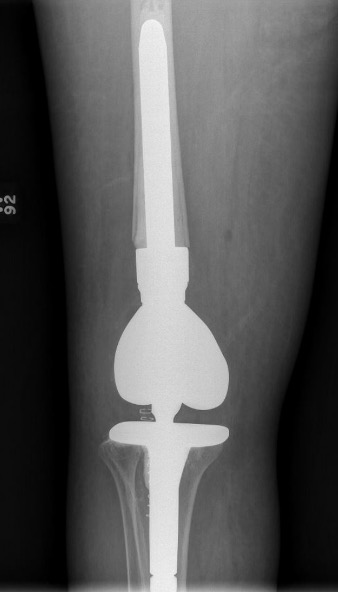

Distal Femoral Replacement

Indications

Elderly osteoporotic patient

Unreconstructable distal femur

Multiple co-morbidities

Difficulty non weight bearing

Results

Hart et al. J Arthroplasty 2017

- ORIF v distal femoral replacement in patients > 70 years old

- reoperation rate 10% in both groups

- 20% non union in ORIF

- at one year, 1/4 ORIF patients wheelchair bound, all DFR patients ambulatory

- AOANJRR review of DFR in native knees

- 10% revision rate at 3y

- most commonly loosening > infection